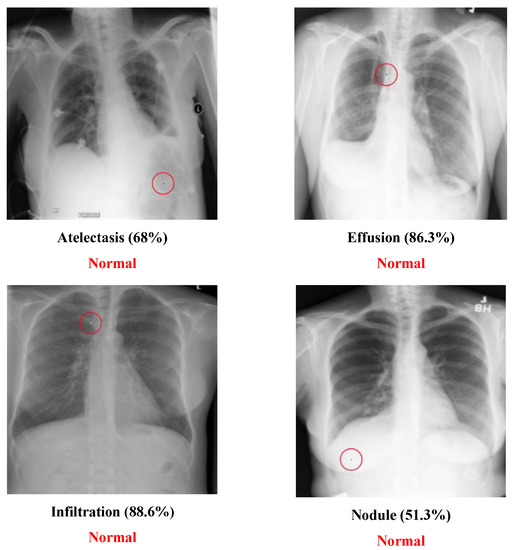

5.2. Multi-Label Dataset

The Chest dataset is a multi-label dataset. Some successful attack examples are shown in Figure 8. The class “Normal” has no confidence level because it means that all labels’ confidence level is below 50%. Figure 9 illustrates some images transformed from a diseased class to a normal class.

Figure 8. Successful chest attack examples.